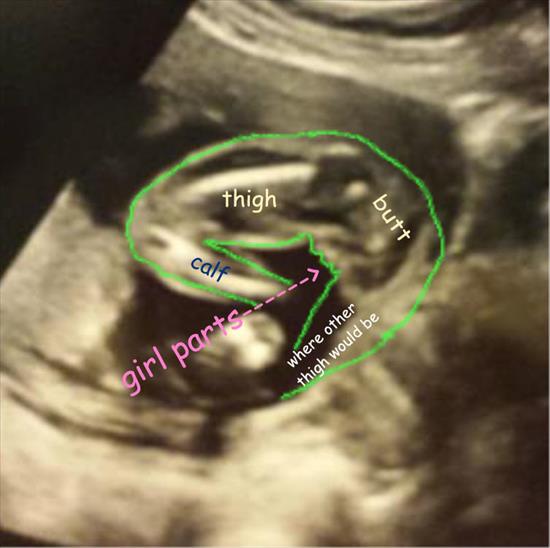

What do you guys see anything? Girl? Boy? Unclear?

I can upload a picture where someone showed what they see

Is this pic accurate?

Is the depicted picture accurate

so hard to be clear on this one the angle is way off. Could be girl parts or scrotum only.

I would not be satisfied with this as a gender shot. I'd want an arrow because honestly, that is not at all how I looked at the picture, although I can see how it could be the correct way to read it. The calf bone is throwing me off since it's so prominent. I *can* see potential girl parts if that is, in fact, the way the picture was shot. But I don't find the picture to be clear. Sorry.